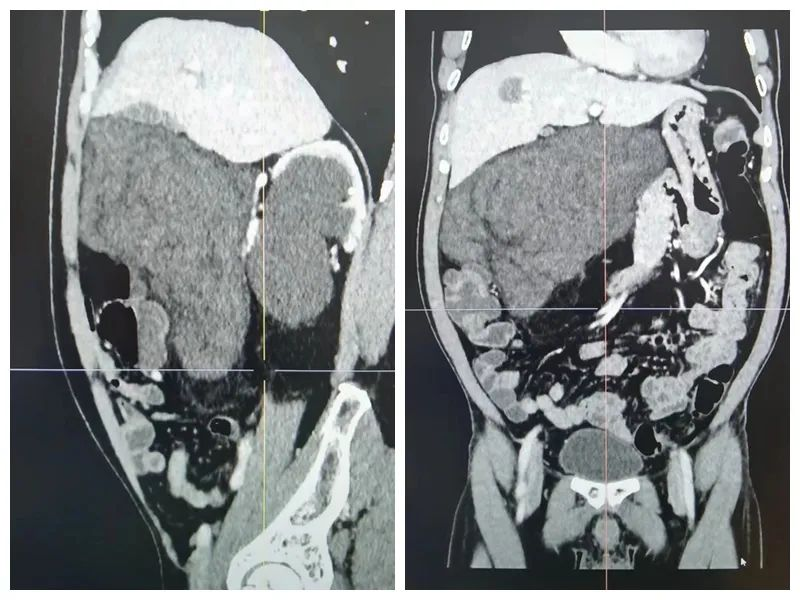

患者赖先生,60岁,感觉春节后“肥胖”不少,腹部逐渐隆起,在家人催促下到医院检查,惊讶发现腹膜后隐藏一个巨大肿瘤,辗转多家医院就诊,最后来到市人民医院胃肠外科和疝外科。患者住院后,仔细回忆病史:10年前曾经在腹部切除一个“脂肪瘤”,由于时间太久,具体情况已记不清楚了,CT检查提示右侧中上腹巨大占位,约206×110×165mm(左右径×前后径×上下径),并且合并右肾重度积水及右肾结石及右侧输尿管上段多发结石并上段慢性炎症,以及右侧腹股沟疝等多个疾病,结合病史及检查考虑右侧腹膜后巨大脂肪肉瘤(复发),考虑肿瘤巨大及位置特殊且合并多个疾病。

术前CT